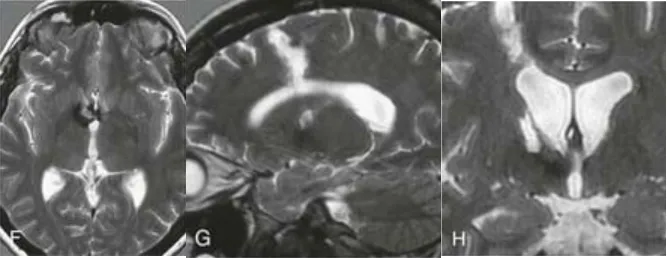

严重的头痛、呕吐,居然查出两个单独的海绵状血管瘤:一个位于右侧额叶脑室旁区(箭头),另一个位于第三脑室Monro孔。

当手术顺利完成,术后CT(E)和MRI(F-H)证实,两个病灶已被完整切除。关键的是,术后没有出现任何新的神经功能或认知障碍!而术者正是巴特朗菲教授。